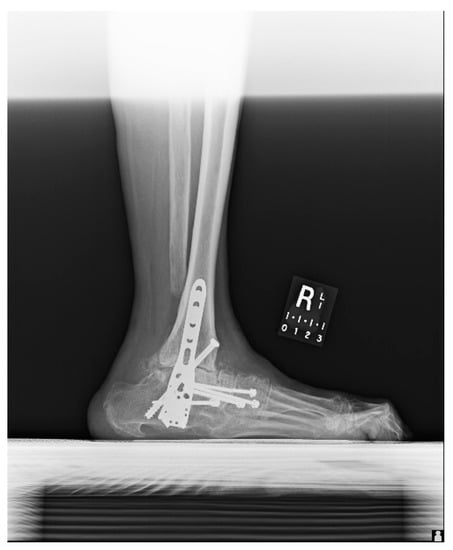

1.1.4. Post-Operative Imaging